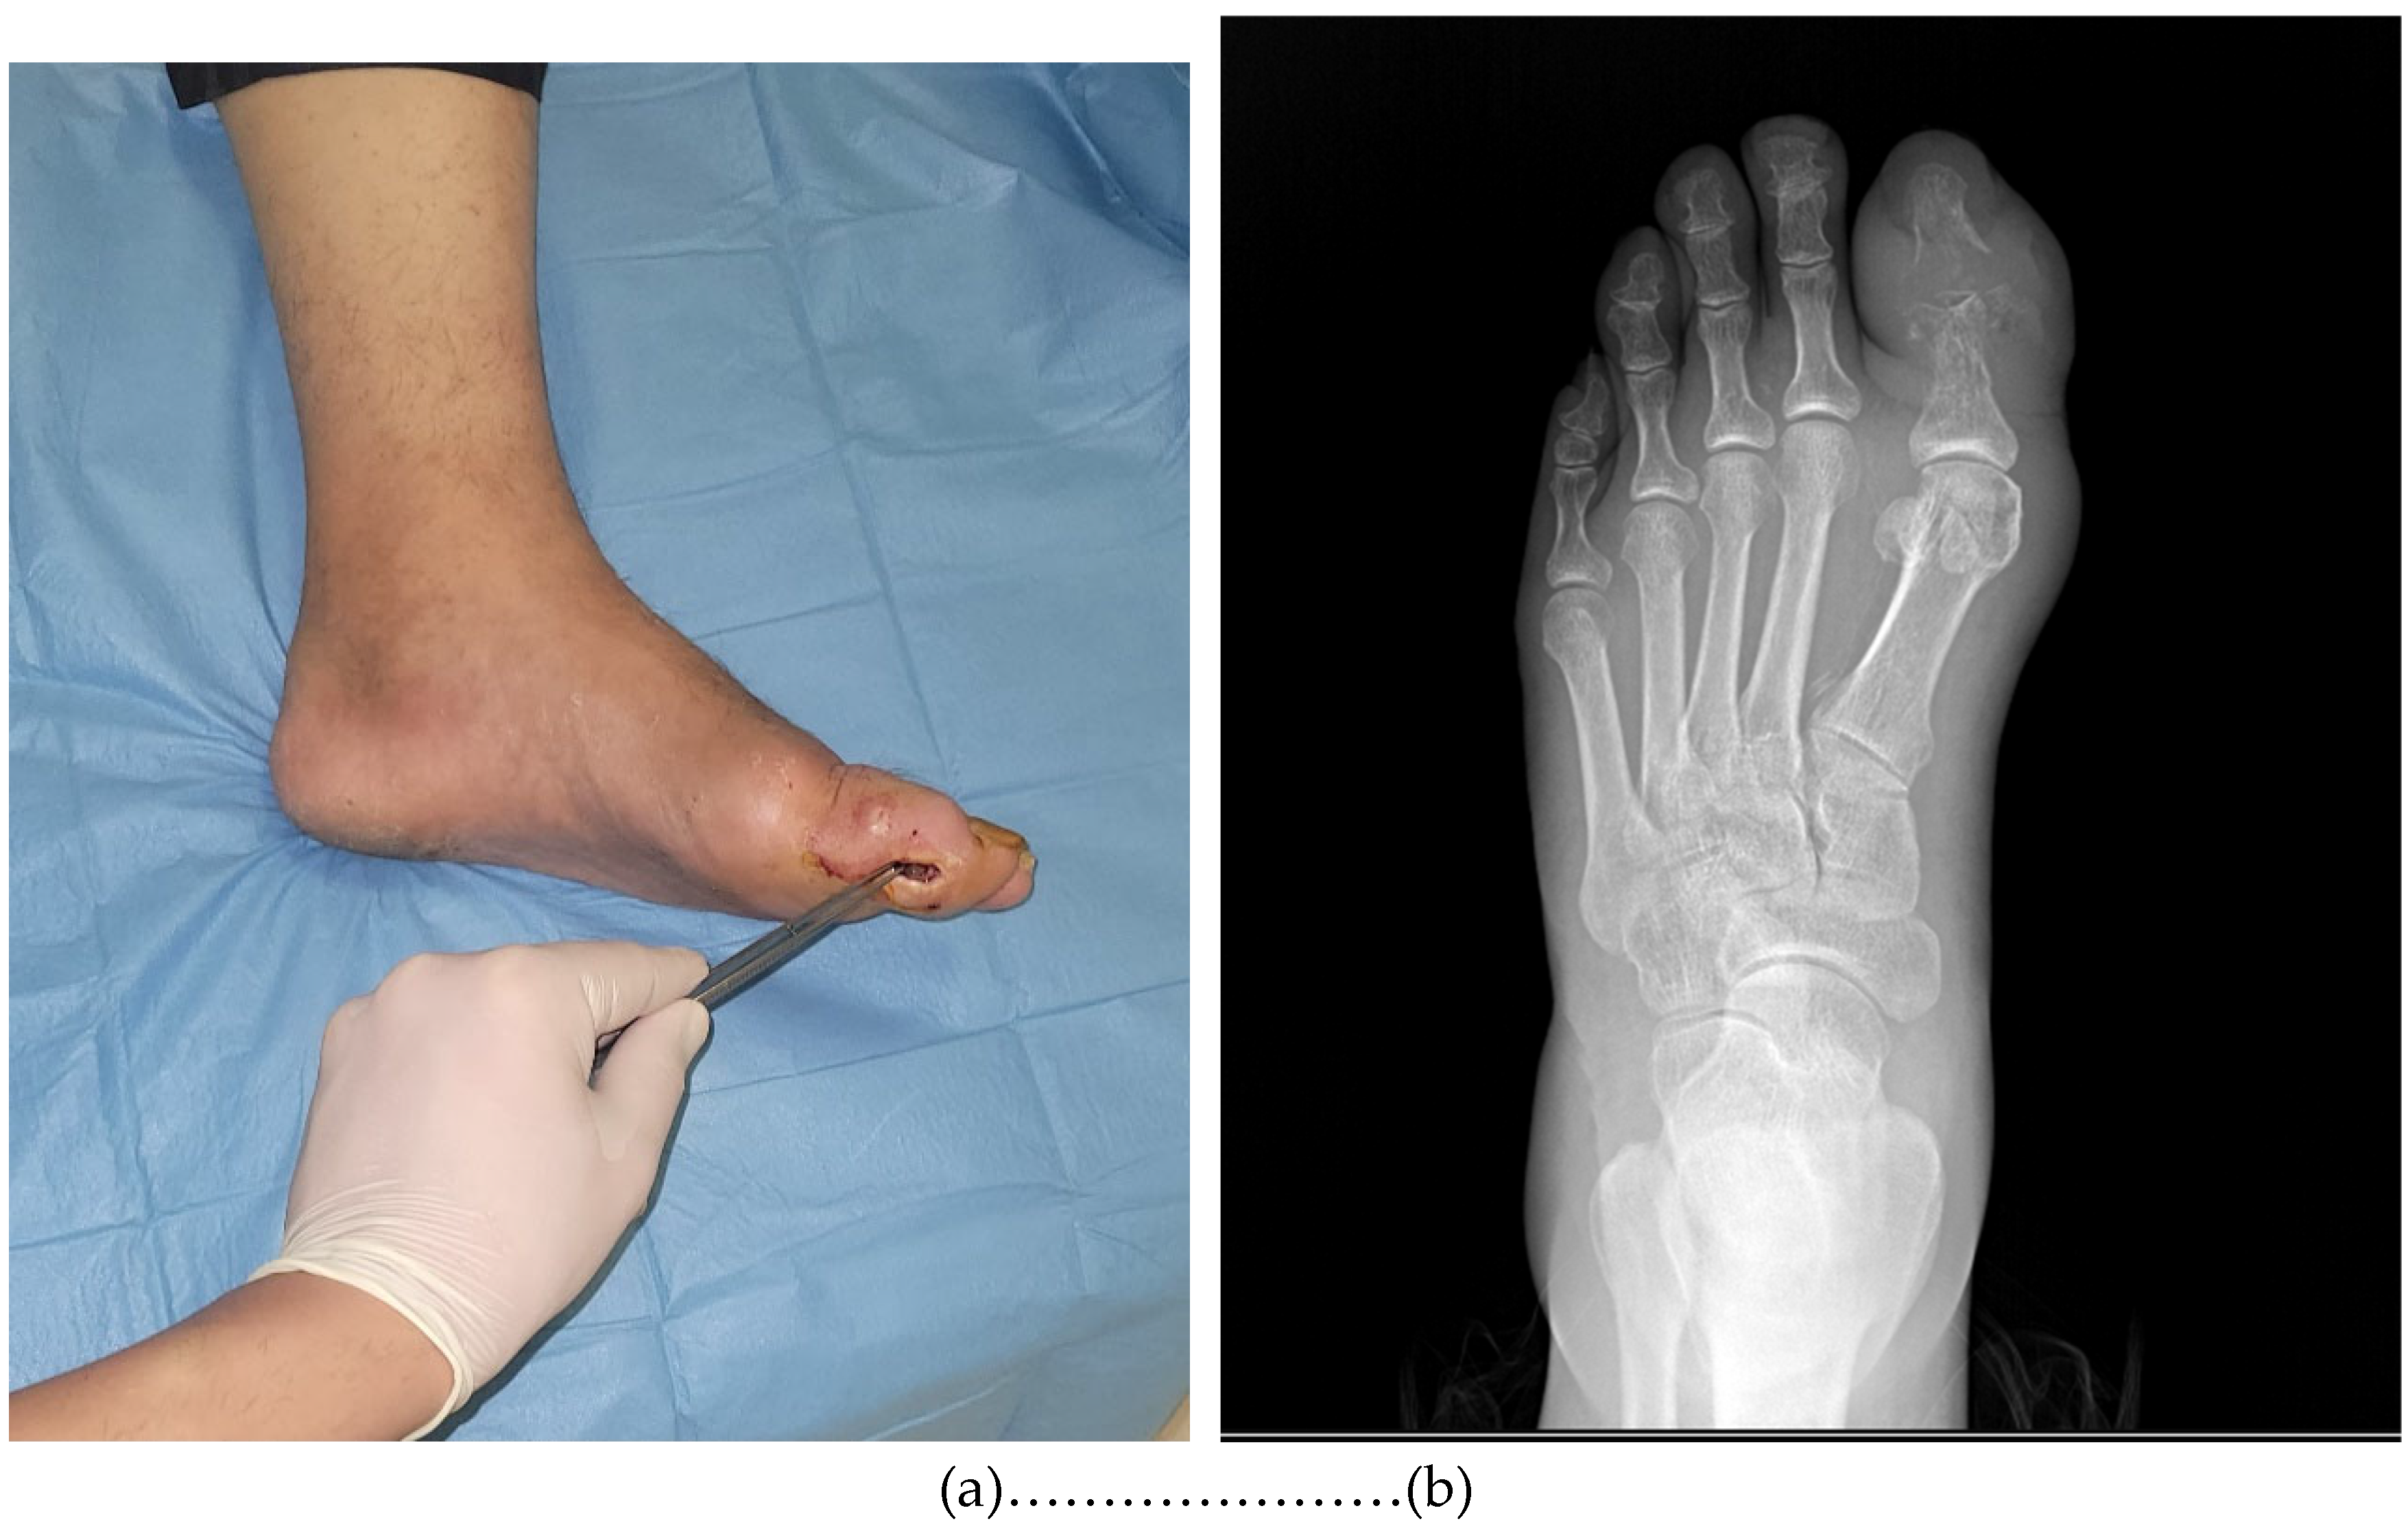

- Positive probe-to-bone (PTB) test (performed using a sterile blunt metal probe; considered positive when bone was palpable through the ulcer);

- Radiographic evidence of osteomyelitis (presence of suggestive findings in initial or follow-up X-rays);